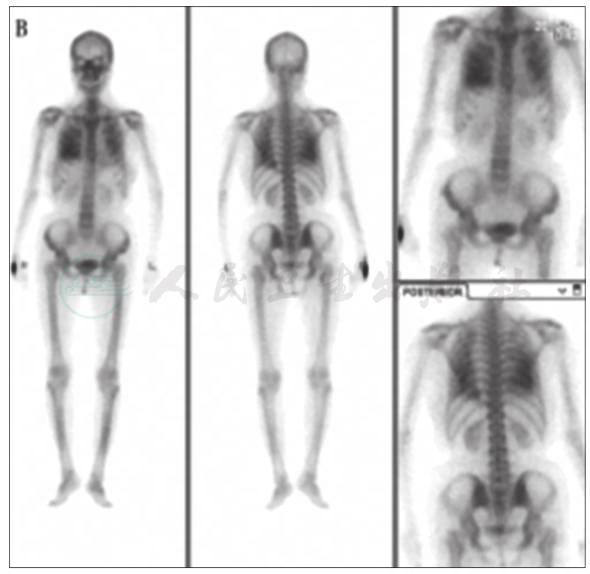

99mTc-MDP骨闪烁显像:双肺野可见类似骨显像影(图7)。

图7 99mTc-MDP骨闪烁显像

引自:主编:.呼吸系统疑难病例诊疗辨析.第1版.ISBN:978-7-117-26415-0

术后11个月,胸部CT示双肺多发斑片影明显减少,左下肺钙化及心室壁钙化较前减轻(图9);99mTc-MDP骨闪烁显像示双肺野骨外显影较前好转(图10)。

图10 术后11个月99mTc-MDP骨闪烁显像

MPC的诊断较困难,特别对于钙-磷乘积正常者,若排除了其他可能引起肺钙化的疾病,如结核、肺泡微结石症、矽肺,需要考虑MPC的可能。99mTc-MDP骨闪烁显像术有助于协助诊断。钙-磷乘积是指血钙、血磷值[以百分毫克(mg/dl)为单位)的乘积,正常值为30~40。其中,[Ca]1mmol/L= 4mg/dl;[P]1mmol/L=3.1mg/dl。若([Ca]×[P])>40,则钙和磷以骨盐形式沉积于骨组织;若([Ca]×[P])<35,则妨碍骨的钙化,甚至可使骨盐溶解,影响成骨。

根据辅助检查结果,考虑本病例病因为原发性甲状旁腺功能亢进,手术切除甲状旁腺,病理检查显示为甲状旁腺腺瘤。甲状旁腺激素分泌过多可致高钙、低磷。本例患者钙磷乘积在正常范围内,经支气管肺活检见肺泡腔及肺泡隔有多量钙化物沉积,胸部CT见两肺散在斑片状影,99mTc-MDP骨闪烁显像见双侧肺野骨外显影,排除了肺结核、矽肺等常见疾病。因此,本病例诊断为甲状旁腺腺瘤伴发转移性肺钙化。

MPC的治疗以控制钙磷平衡为主,积极治疗引起钙磷代谢紊乱的病因,如慢性肾功能不全、原发或继发性甲状旁腺功能亢进等,病情可好转。本病例影响钙磷平衡的主要原因为甲状旁腺腺瘤,手术切除病变的甲状旁腺,术后11个月复查胸部CT显示病灶较前明显吸收。